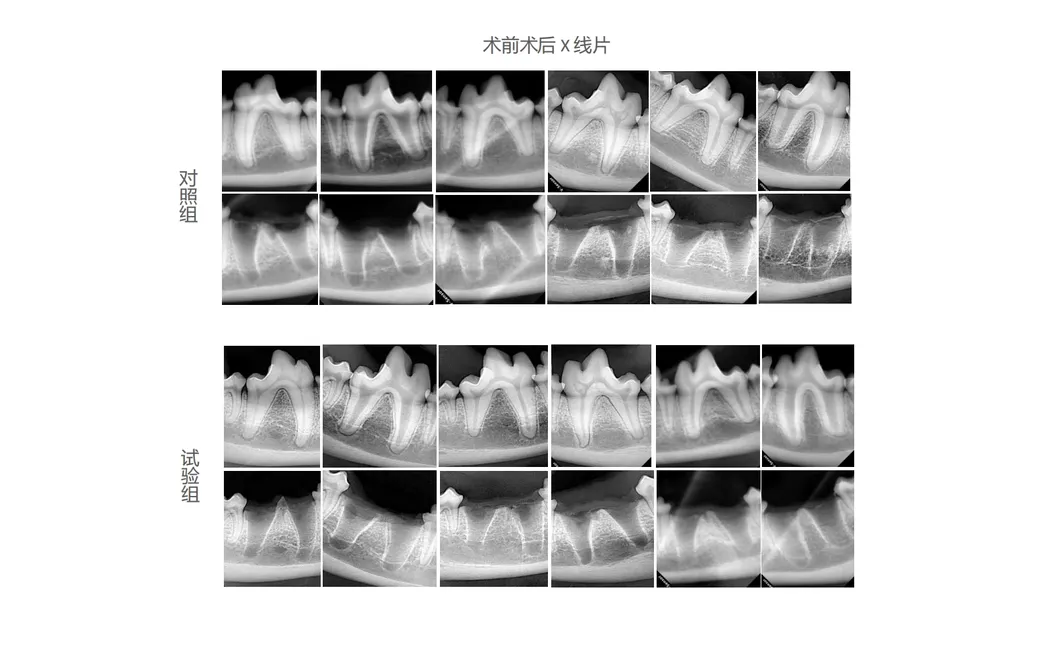

In this study, dogs were chosen as experimental subjects to evaluate the effectiveness of revolutionary dental tools. The study compared traditional manual extraction devices against the state-of-the-art Pneumatic Dental Elevator Kit. Researchers documented physiological parameters, intraoperative complications, extraction duration, and socket damage, alongside postoperative healing and histological evaluations.